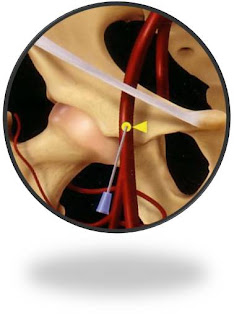

Gambar 1. Posisi anatomi dari CFA

Sebagai batas puncture atau garis imaginer adalah ligamentum inguinal kanan yang melintang dari SIAS (sacroiliaca anterosuperior sampai ke tubercel pubis / ramus superior pubis) gambar (1). Posisi dari CFA adalah 1/3 medial garis imaginer.